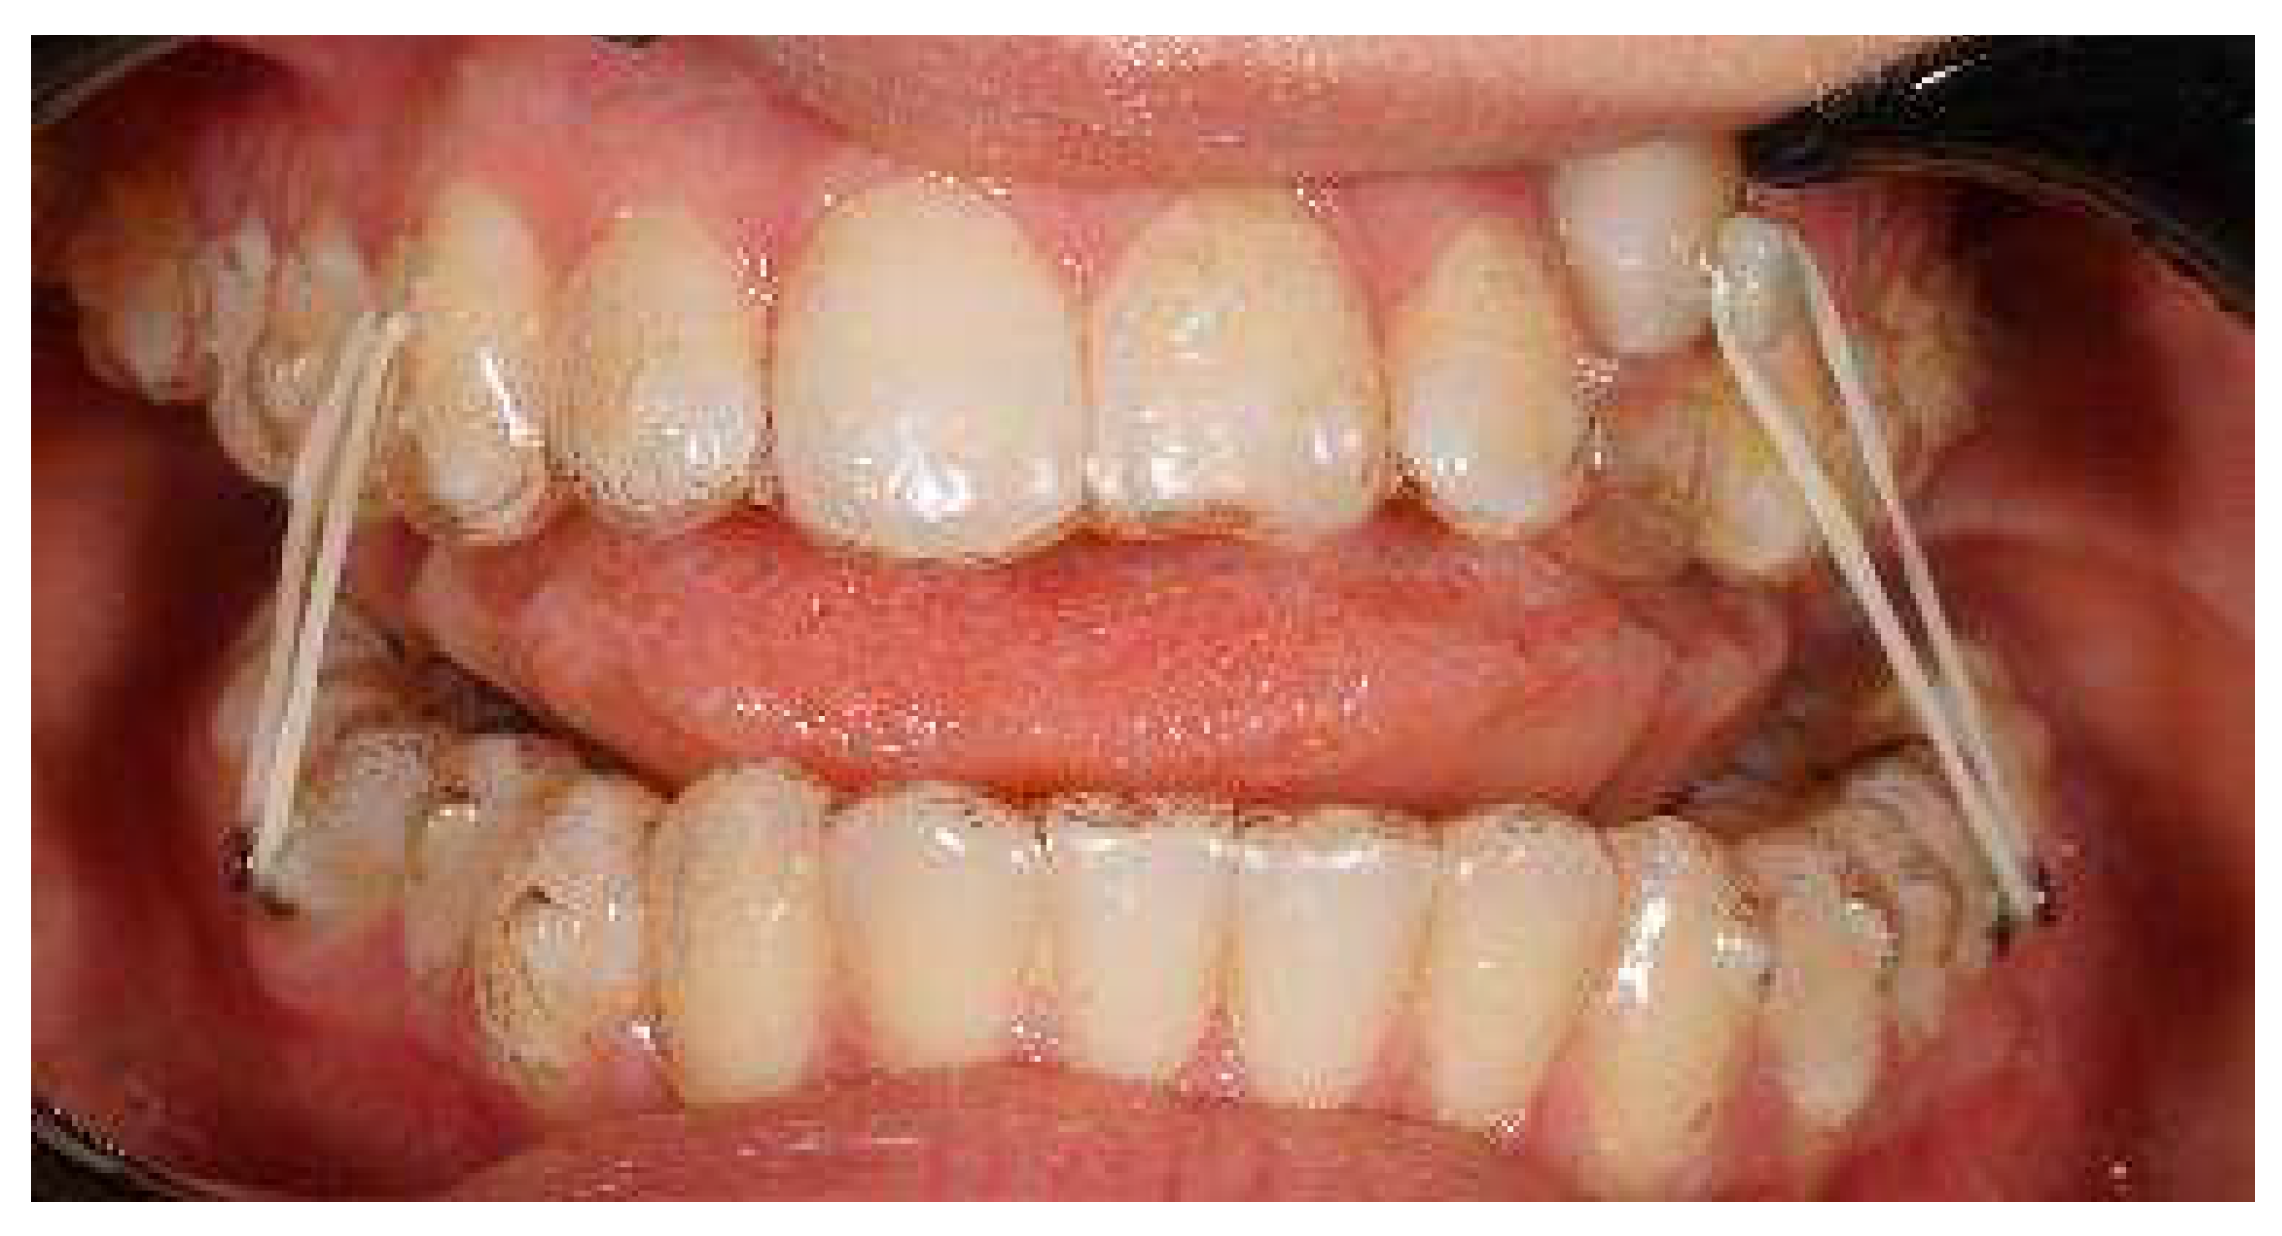

Once the disimpacted canine was in a better position and near to the crest, intraoral impressions and a new series of pictures were taken (Figure 7).

Figure 7.

First refinement with the involvement of the 1.3 in the aligner and consequent alignment and levelling of both arches.

A horizontal rectangular attachment was placed on the buccal surface of the canine and a buccal root torque was applied to ensure the three-dimensional control of the tooth movement (Figure 8).

Figure 8.

Horizontal Rectangular gingival bevelled attachment to improve the fitting on the 1.3 and buccal root torque.